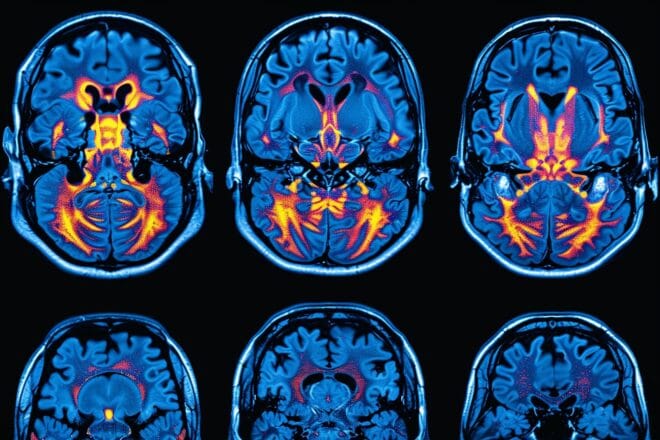

Illustration. Des scintigraphies cérébrales montrent une détérioration progressive due à la maladie d'AlzheimerADN